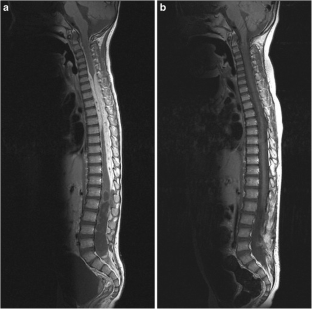

Fig. 2